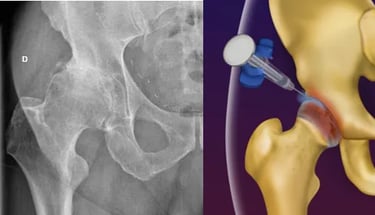

Artrose do Quadril

Apesar de ser uma doença do quadril, alguns pacientes portadores de artrose (desgaste) no quadril podem sentir a dor na coxa, junto com dor no quadril, ou apenas na coxa.

Dessa forma, é importante que caso o exame físico sugira que a dor é oriunda de um problema no quadril, o médico solicite exames do quadril, e não apenas da coxa.

A artrose do quadril é uma condição degenerativa da articulação, que cursa com o desgaste da cartilagem, fazendo com que o paciente apresente dor ao andar e movimentar o quadril.

Faz-se o diagnóstico com RX e Ressonância Magnética.

O tratamento se inicia com medicações analgésicas, perda de peso e Fisioterapia. No entanto, pode-se realizar infiltração com ácido hialurônico na articulação caso o paciente persista com dor na coxa ou dor no quadril.

Com o avanço dos materiais utilizados na cirurgia e nas técnicas cirúrgicas, o paciente volta a ter uma vida normal, praticamente sem limitações após a cirurgia. As próteses mais modernas têm uma durabilidade de aproximadamente 25 anos, permitindo que mesmo pacientes mais jovens possam ser submetidos a essa cirurgia.